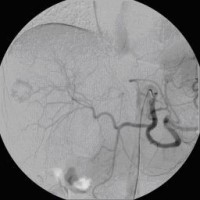

Superselektive transarterielle Chemoembolisation (TACE) mit Sondierung eines tumorversorgenden Gefäßes 3

(Bild 5 von 5)